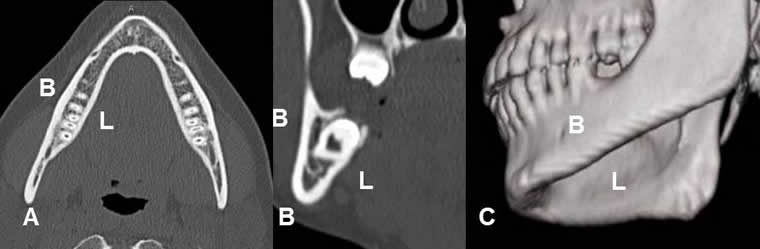

Fig 8. Mandíbula normal.

A: TAC axial y B: TAC coronal y C: TAC reconstrucción 3D. Superficie interna de la mandíbula o lingual (L) y externa o bucal. (B).